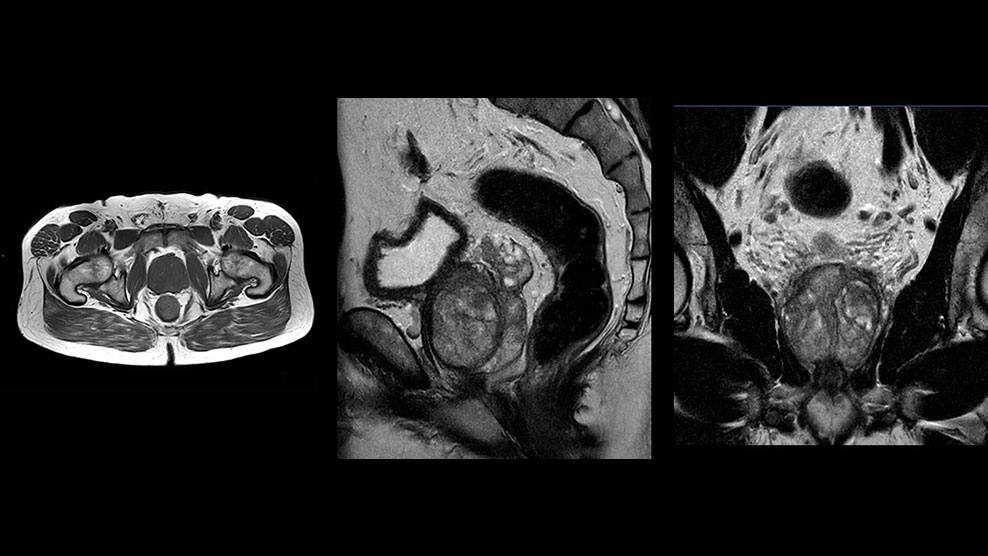

Patrick Duffy BS, RT (R) MR is Lead Technologist at DMG. “We are getting phenomenal image quality on all types of exams,” he says. “Our MSK is stellar, and so is our abdominal work. Ingenia excels at feet, hands and fingers. We do enterographies with great results. With the combination of the 3.0T magnet and the digital coils, we are able to scan prostates without an endorectal coil while still obtaining high quality results. This is a comforting experience for our male patients. We scan many obese patients, and the Ingenia does a tremendous job because of MultiTransmit, which reduces dielectric shading for more confident diagnosis. Our technologists really enjoy scanning on the Ingenia. We also have ordering physicians who specifically want their patients scanned on the Ingenia because of the results of our imaging.

“Obviously, the diagnostic capability is most important,” says Dr. Kaakaji. “Ingenia’s image quality is excellent and in follow-up studies, Ingenia provides good consistency between scans.

“Without using an endorectal coil we do our prostate MR at 0.5 mm resolution, following the European society of urology protocol [1]. For certain joints we use a virtual arthroscopy protocol with 1 mm pixel size and 2 mm slice thickness. Ingenia really excels in our neurography, brachial plexus and prostate scans. Our neurologists insist on using our 3.0T for those,” Dr. Kaakaji adds.